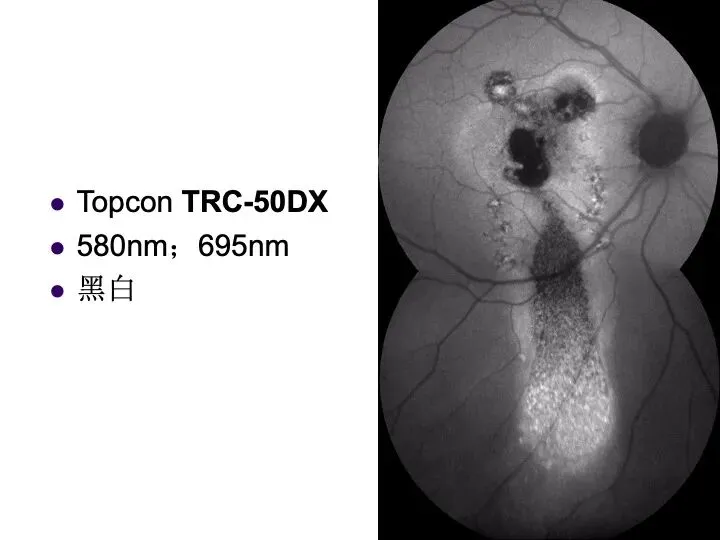

>2009年长沙眼底病会议 - “光学影像检查”面世

2009年,距今已经过去快20年了。当时是首次提出“

眼底光学影像检查

”的概念,可惜,还是影响力不足,这个概念近年来被“

多模眼底影像

”所取代。回顾当年的幻灯,还是感觉有其内在生命力,仍然可以供大家参考。

对比上述两个概念,本人还是偏爱“

”,后者虽然是从国外舶来,但是其定义、内涵好像不如前者清楚。也希望同道指正、发表高见。